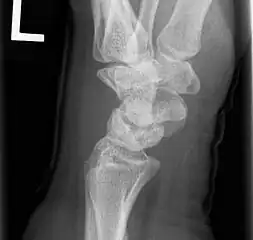

X-ray showing stage IIIB on right wrist, with ulnar impingement.